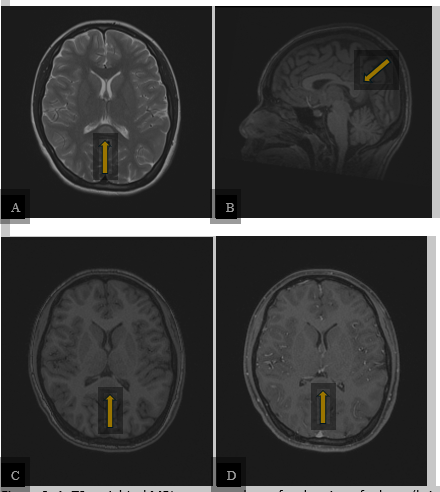

Magnetic Resonance Imaging (MRI) of the brain was performed and demonstrated a focal region of edema (bright T2 signal) within the splenium of the corpus callosum in the midline. This lesion was dark on T1 and showed no enhancement following intravenous contrast administration (Figure 2).

Figure 2: A. T2-weighted MRI sequence shows focal region of edema (bright signal) within the splenium of the corpus callosum in the midline (arrow). B. and C. This lesion was dark on T1-weighted sequence (arrows). D. The lesion showed no enhancement following intravenous contrast administration on the T1 post-contrast sequence (arrow). The rest of the brain was normal.